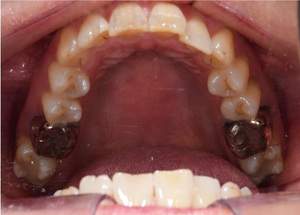

症例写真(治療前)

治療前:

八重歯が目立ちます。また銀歯もおおく、見た目が気になります。虫歯も散見できます。

症例写真(治療後)

治療後:

矯正治療と虫歯の治療すべて終わったときの写真になります。見た目も最初の頃とは全く違いますし、お口の中もすごく綺麗です。